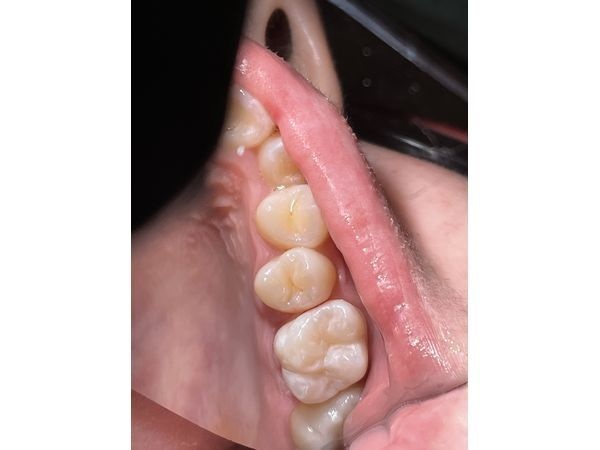

- установили пломбу Estelite quick (комбинация оттенков 0А3 и 0А2) и скорректировали с учётом прикуса;

- отполировали зуб специальными резинками, чтобы поверхность стала гладкой и глянцевой.

Действие анестезии прошло спустя полтора часа после манипуляции. На следующий день девушка пришла на осмотр, чтобы выявить суперконтакты между новой пломбой и противоположными зубами, т. е. проверить, не мешает ли пломба правильно смыкать челюсти.

В результате лечения болезненность больше не беспокоила. Анатомическая форма и цвет зуба были восстановлены. Пациентке также рекомендовали сделать профессиональную гигиену и проходить осмотр каждые полгода.